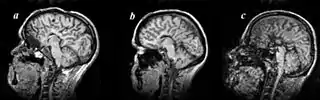

Image indicates colpocephaly with septal agenesis

Colpocephaly is characterized by disproportionately large occipital horns of the lateral ventricles (also frontal and temporal ventricles in some cases). MRI and CT scans of patients demonstrate abnormally thick gray matter with thin poorly myelinated white matter. This happens as a result of partial or complete absence of the corpus callosum. Corpus callosum is the band of white matter connecting the two cerebral hemispheres. The corpus callosum plays an extremely important role in interhemispheric communication, thus lack of or absence of these neural fibers results in a number of disabilities.[12]